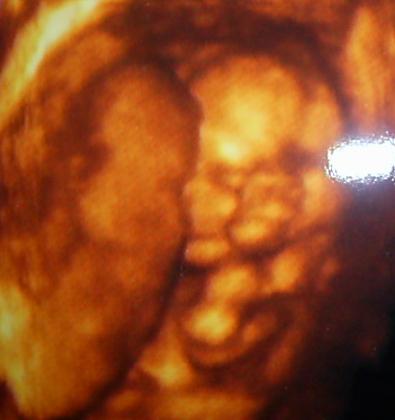

A kepek alapjan tenyleg hatalmas a pocid

es hat valoszinu a baba sem kicsi

nagyon szep pocid van,es hat nem kicsi!!!!